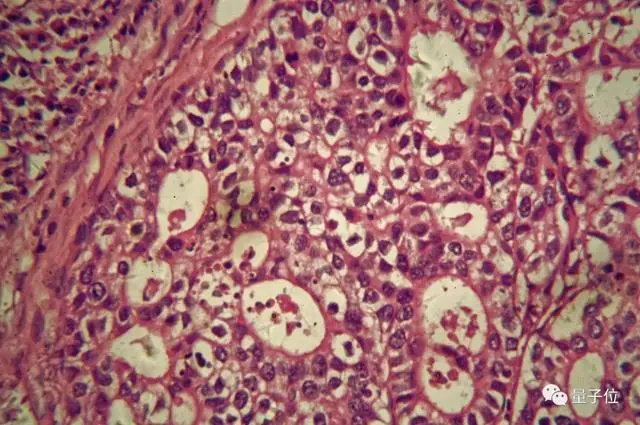

此前观察癌细胞,效果是繁杂累眼的:

而谷歌的显微镜,开挂了:

在这台显微镜下,以淋巴结和前列腺结节的样本,分别在10倍放大和20倍放大下做实验,发现可以成功的标注出有癌细胞的地方。